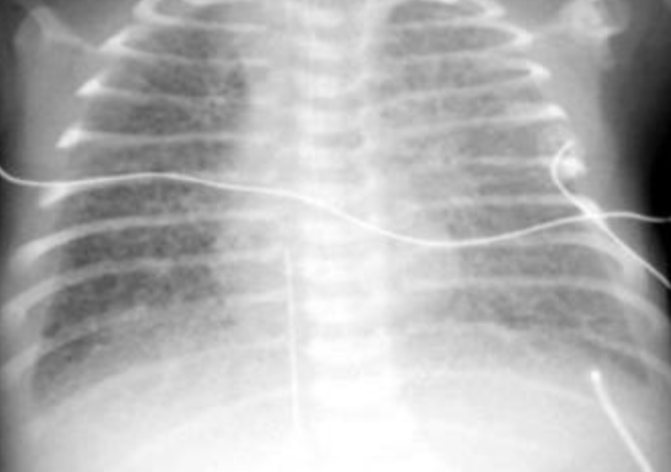

- Anterio-posterior [AP] chest radiograph shows multiple cystic lesions inâ (1 -the middle and lower zones of the left hemi-thorax with ill-defined left hemi diaphragm. There is mediastinal shift toward the right. These lesions are -bowel loops inside the left hemi-thorax. The film is over exposed (over .(penetration

- The diagnosis is Left Sided Congenital Diaphragmatic Hernia (CDH). This - (2 is called bockdalic CDH. CDH is usually in the left side (90 %). The defect is found in the posterio-lateral aspect of the diaphragm. CDH is associated with .lungs hypoplasia in the same side and to a lesser extent in the opposite side .This may be complicated by pulmonary hypertension and severe hypoxemia

- The treatment of CDH is immediate endo-tracheal incubation if it is - (3 diagnosed in-utero or if it is highly suspected after birth (with following symptoms and; respiratory distress (RD), cyanosis, asymmetrical chest movement, bowel sounds heard in the chest and scaphoid abdomen). After intubation, the patients is put on mechanical ventilator and the pulmonary hypertension [PH] is controlled and hypoxemia is reversed. PH and severe hypoxemia may require inhaled Nitric Oxide [iNO], High frequency Oscillatory Ventilation [HFOV] and Exogenous Surfactant administration through endotracheal tube [ETT]. After the stabilization of the arterial blood gases the patient is taken to suture the defect. If the defect is large, a mesh,[ABGs] device may be used. The most important differential diagnosis is Cystic .Adenomatoid Malformation [CAM]